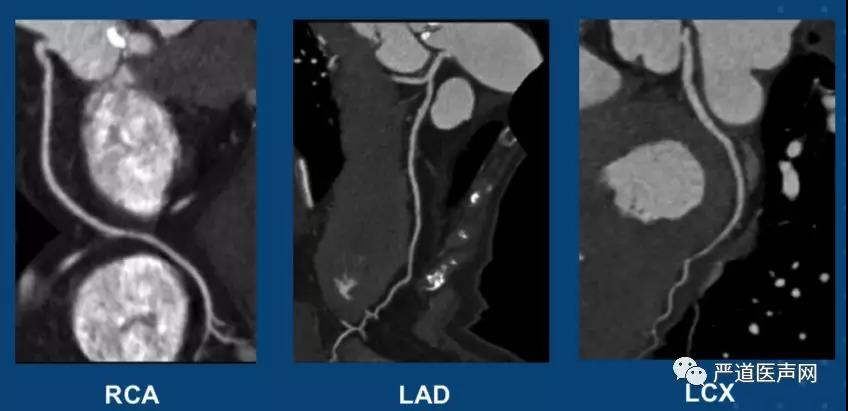

瓣环结构(收缩期)

Type 0 型二叶式主动脉瓣畸形

瓣环平面 周长平均径 20.5mm

主动脉窦30.6mm×21.9mm

冠状动脉管腔轻度狭窄,不需要干预。

冠脉开口高度高(LC 16.7mm; RC 18.3mm),瓣叶重度钙化。